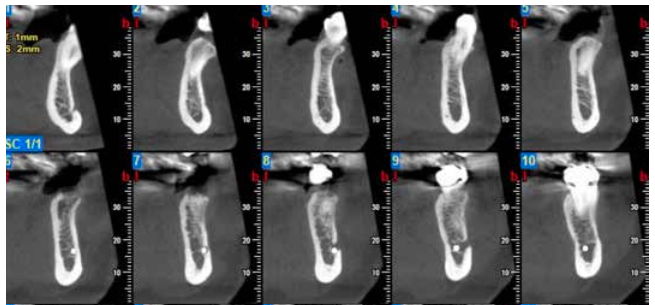

Materials and methods: A study was carried out on 6 patients from the Faculty of Dentistry of the Complutense University of Madrid performing the technique of alveolar ridge preservation. Two groups were established, a test group in which the alveolar socket was filled with calcium phosphate and added silicon and a control group where the socket was filled with bovine hydroxyapatite. After 3 months, a cone-beam computed tomography was performed to evaluate the bone density achieved by both biomaterials.

Results: The average bone density achieved in the group treated with calcium phosphate and added silicon was 1100,40 ± 111,19 Hounsfield units whereas in the group treated with bovine hydroxyapatite the average bone density was 1029,46 ± 95,16 Hounsfield units.

Conclusions: Both biomaterials seem to present a similar behaviour in terms of densitometric results obtaining a density greater than 1000 Hounsfield units, having the calcium phosphate and added silicon the highest density.